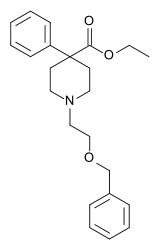

4-Phenylpiperidines

Pethidines (meperidines)

- Etoxeridine (carbetidine)

Structures